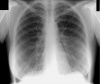

Важное объявление!Приглашаем всех желающих пройти флюорографическое обследование, так как в период с 1 июня планируется замена флюорографического и рентгенологического оборудования... 7 апреля 2022 - 14:12